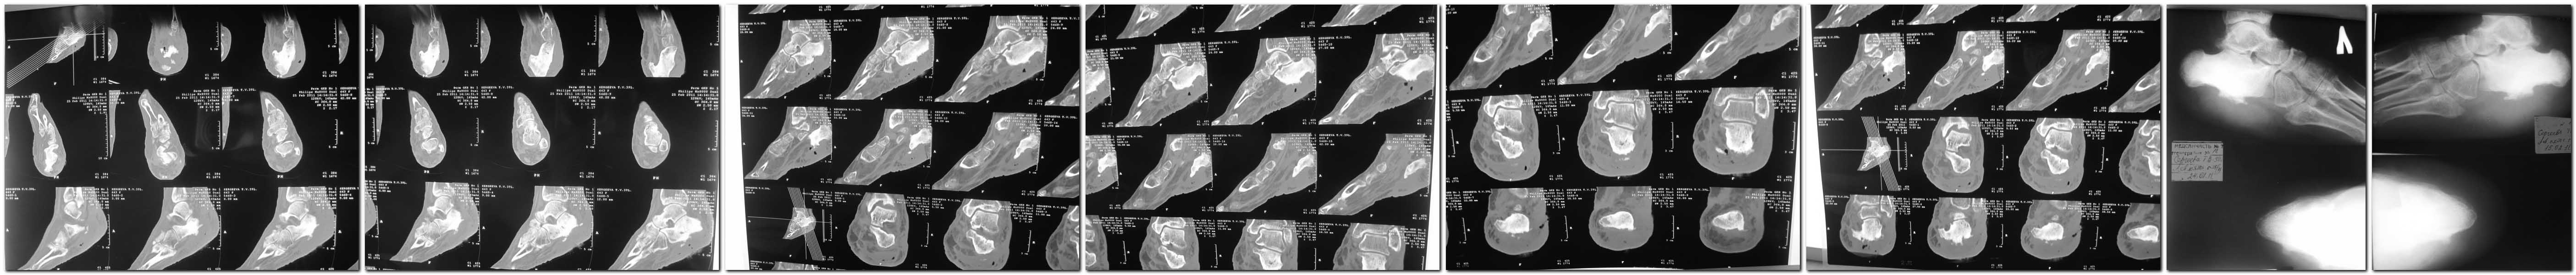

Re: хронический остеомиелит пяточной кости

получше разрешение у КТ и Р-грамм